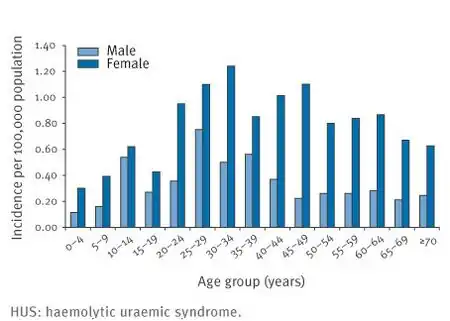

| Risk factors | Younger age, female[1] |

Hemolytic–uremic syndrome (HUS) is a group of blood disorders characterized by low red blood cells, acute kidney failure, and low platelets.[1][3] Initial symptoms typically include bloody diarrhea, fever, vomiting, and weakness.[1][2] Kidney problems and low platelets then occur as the diarrhea is improving.[1] While children are more commonly affected, adults may have worse outcomes.[2] Complications may include neurological problems and heart failure.[1]

Treatment involves supportive care and may include dialysis, steroids, blood transfusions, or plasmapheresis.[1][2] About 1.5 per 100,000 people are affected per year.[5][1] Less than 5% of those with the condition die.[1] Of the remainder, up to 25% have ongoing kidney problems.[1] HUS was first defined as a syndrome in 1955.[1][7]

STEC-HUS most often affects infants and young children, but also occurs in adults. The most common form of transmission is ingestion of undercooked meat, unpasteurized fruits and juices, contaminated produce, contact with unchlorinated water, and person-to-person transmission in daycare or long-term care facilities.[24]

In the United States, the overall incidence of HUS is estimated at 2.1 cases per 100,000 persons/year, with a peak incidence between six months and four years of age.[57]